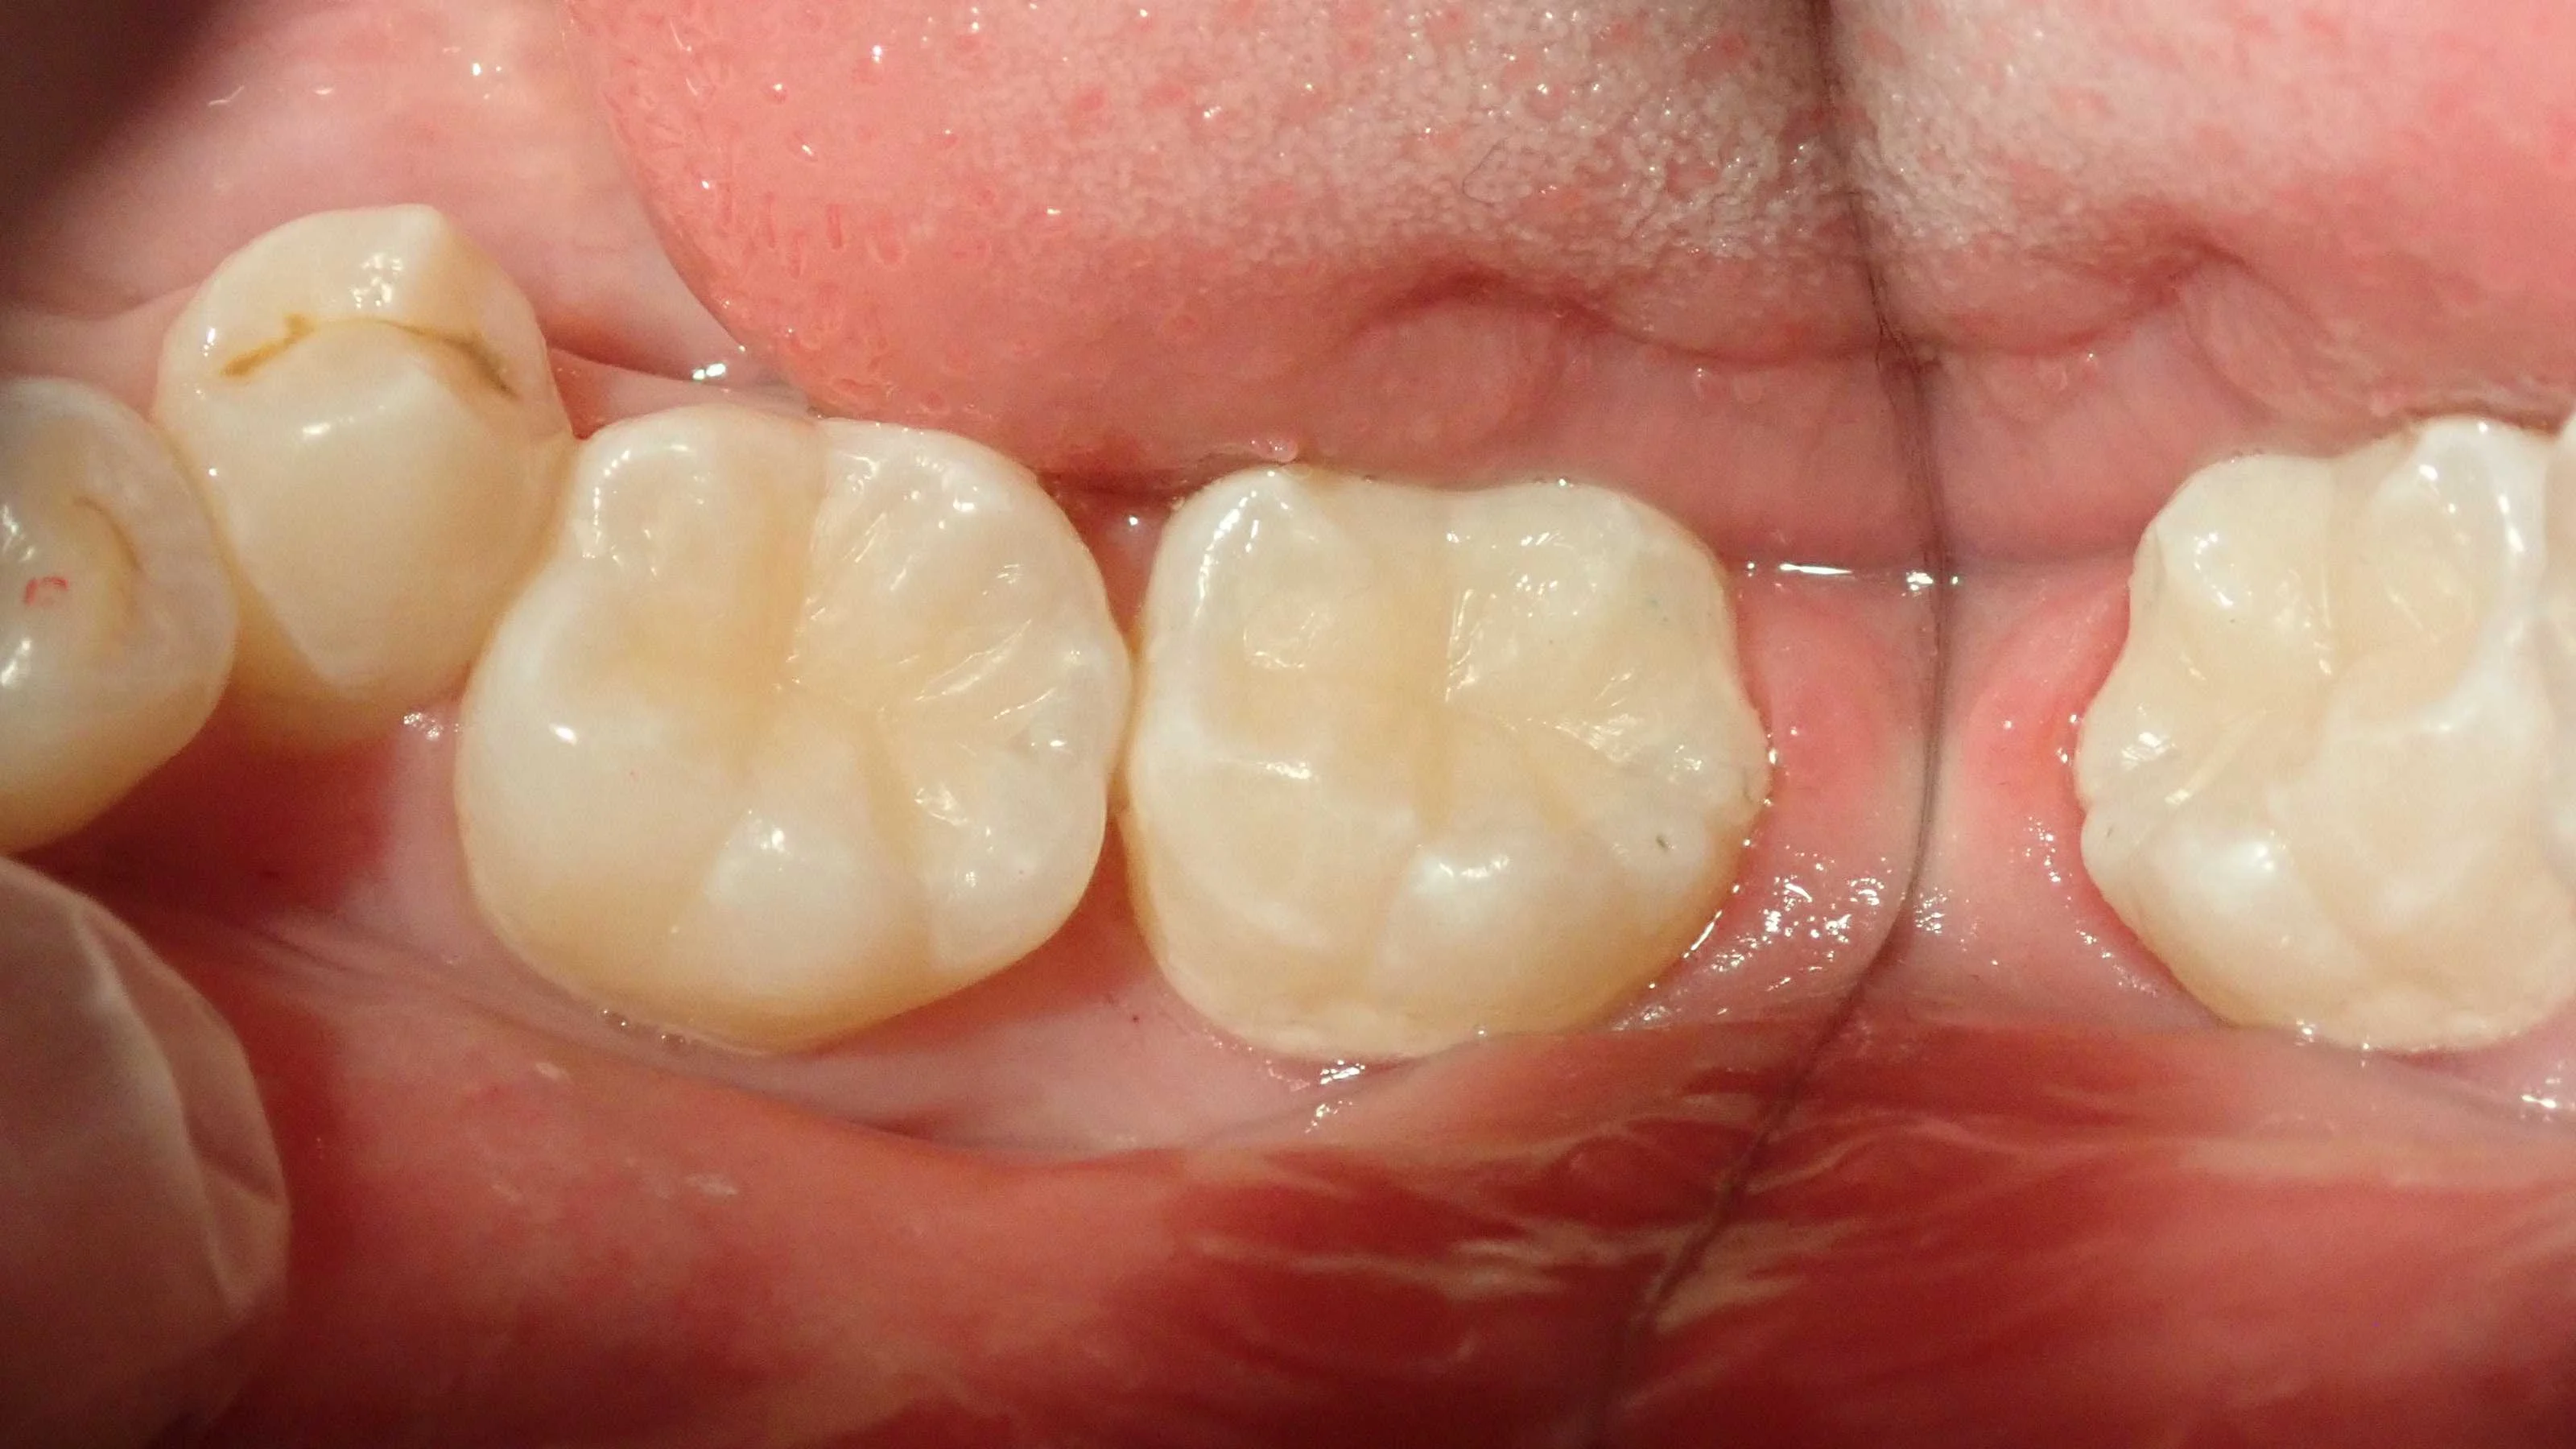

術後です。

よくコンポジットレジンの治療をされた歯を見ると、咬合面(物を噛む面です。要は真上です。)に溝を入れていないケースを多々目撃します。

(ちなみにこの溝のことを裂溝と言います。)

歯科医師にはこの裂溝を再現する先生としない先生の2パターンが居ます。

写真でもお分かりかと思いますが、私は保険だろうが自費だろうが再現するタイプです。

理由としては、

・・・これだけ長い間、人類の進化上で消えていない以上、なんか意味ある・・・よね?

程度のものです。

あとはまぁ、見た目もこっちのほうが綺麗なんで再現するようにしています。